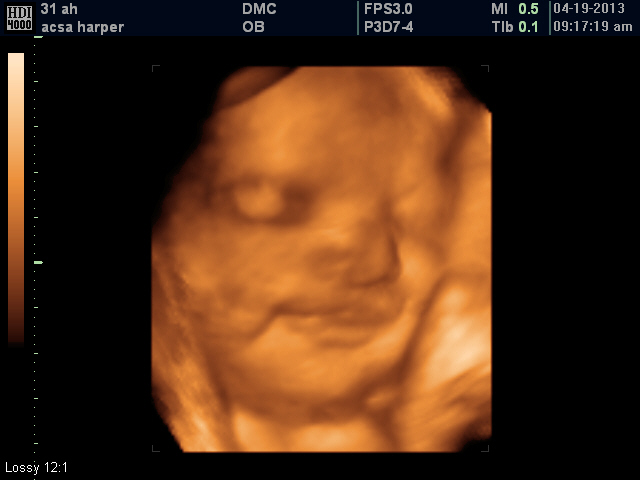

Here are a few photos of the scan:

| She had her arms behind her head and was sound asleep. |

Since she wasn't waking up,my husband got real close and told her to wake up and we got a huge smile!!She adores her daddy.

| This face!!! I absolutely love it! |